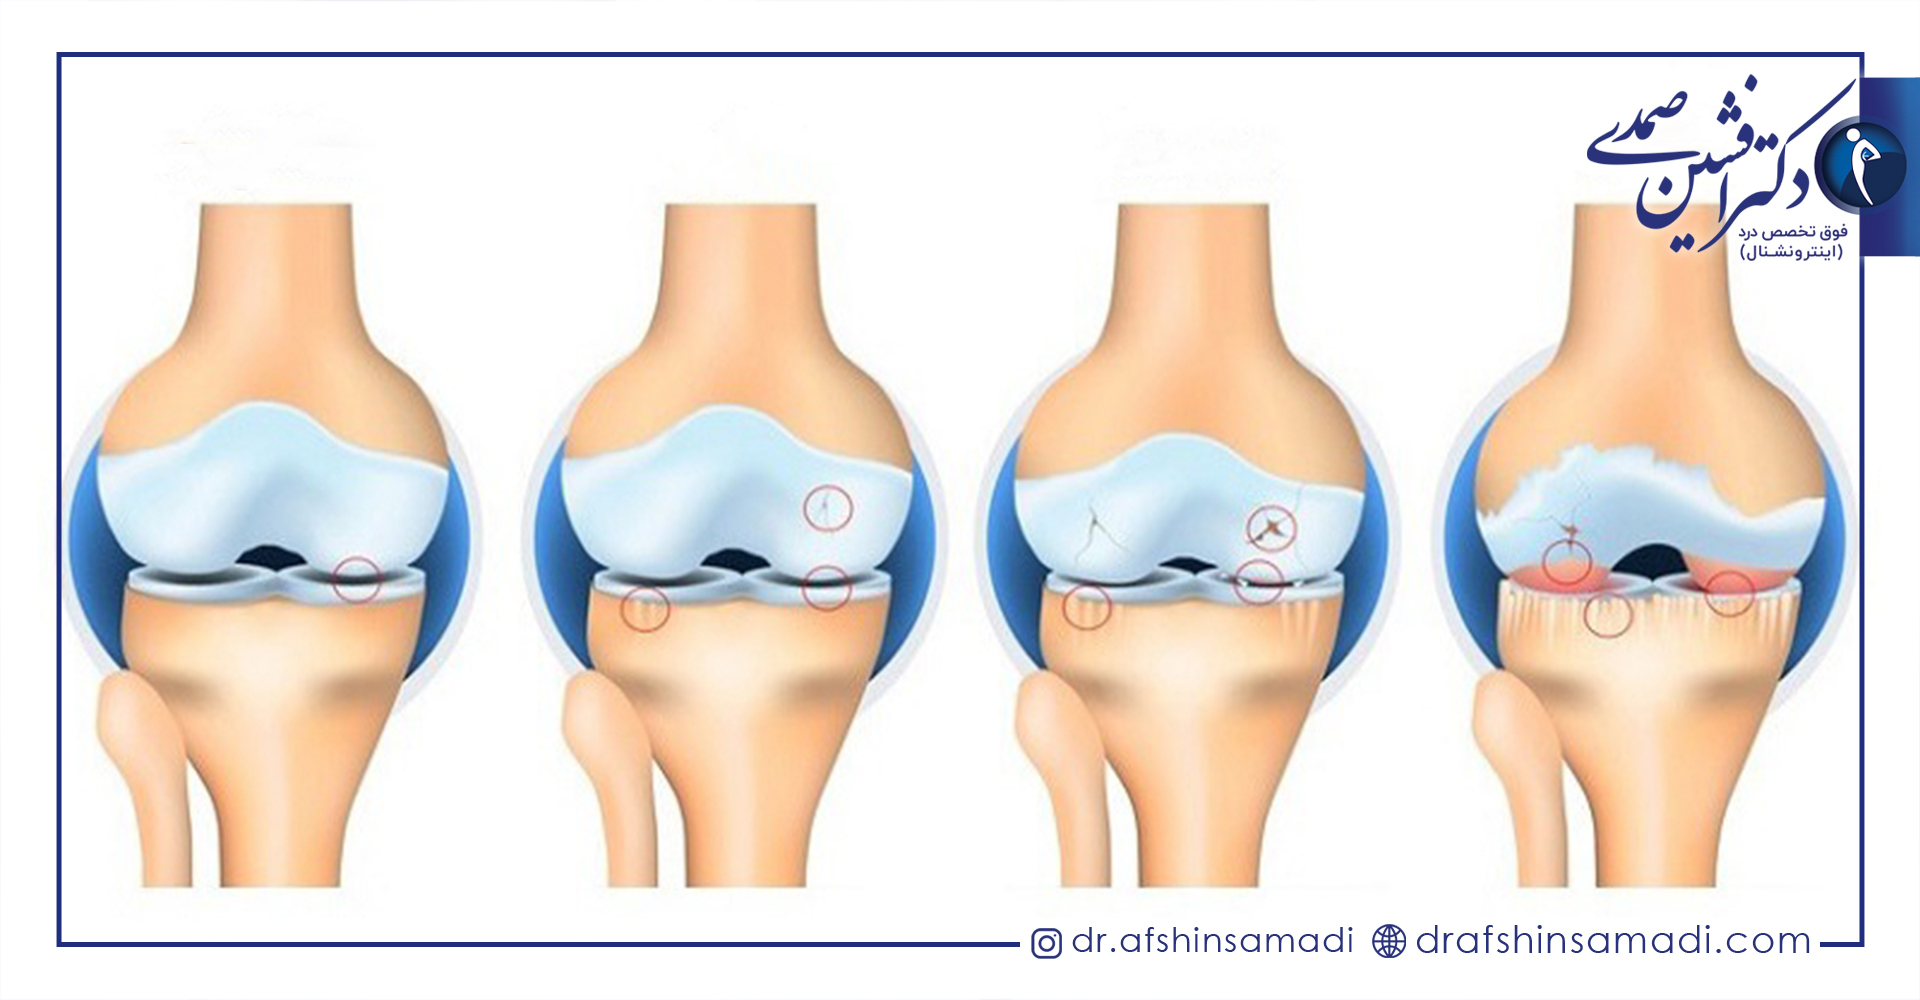

غضروف ها ماده ای نرم در میان مفاصل بوده که از ساییدگی استخوان ها بر روی یکدیگر جلوگیری می نمایند.

در بیماری استئوآرتریت غضروف میان مفاصل از بین رفته و استخوان های قسمت مفصل ها دچار آسیب دیدگی میشود.

این بیماری با ساییدگی، فرسودگی و از بین رفتن غضروف همراه است و در صورت ابتلا، فعالیت های روزمره شخص دچار مشکل می شود و باعث بروز درد می گردد.

زمانی که غضروف های موجود در انتهای استخوان ها دچار آسیب دیدگی شده و تحلیل روند، استئوآرتریت بروز می یابد و با از بین رفتن کاملا آن، دو استخوان بر روی همدیگر قرار گرفته و دچار ساییدگی میشوند.

این بیماری علاوه بر اینکه باعث تخریب غضروف می شود، بر روی کل مفصل های بدن اثر گذاشته و استخوان را دچار تغییر می کند.